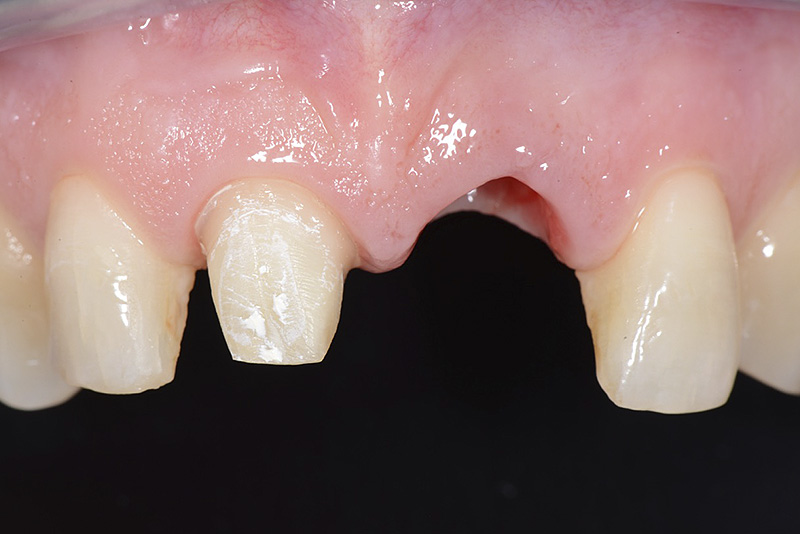

Vengono utilizzati 2 tipi di provvisori: il primo, cementato ai denti vicini, viene utilizzato dal momento dell’estrazione del dente fino ad impianto osteointegrato (circa 6 mesi); il secondo, avvitato direttamente all’impianto, ha una funzione di prova estetica ma soprattutto di guida per la maturazione dei tessuti gengivali peri-implantari portandoli verso la maturazione completa prima di posizionare la corona finale in disilicato di litio.